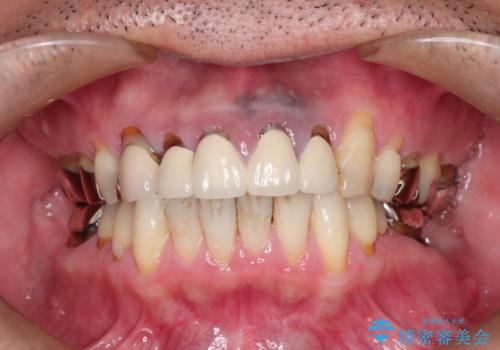

[フルジルコニアクラウン] 老朽化した銀歯を白く